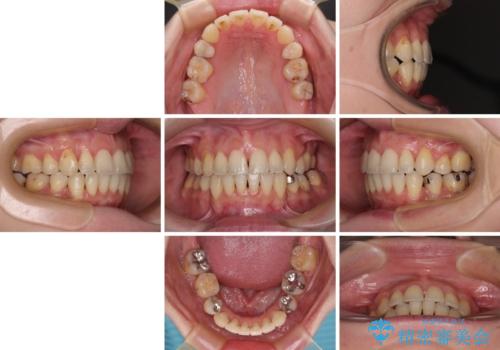

【モニター】上下の八重歯を治したい ワイヤー装置による矯正治療

- 上下前歯のデコボコを気にして来院された患者様です。

デコボコが強いため、非抜歯で矯正をすると出っ歯仕上がりとなるため、上下左右の第一小臼歯4本を抜歯することとしました。

治療期間全体を通して歯の移動スピードがゆっくりであったので、当初予定よりも1年ほど長い、3年間を要することとなりました。